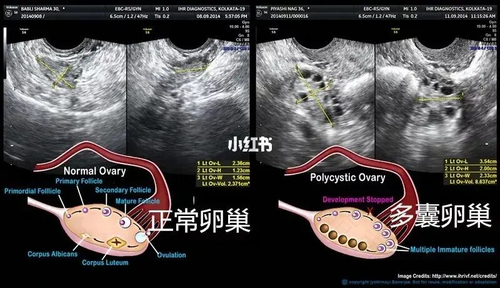

卵巢多囊综合症对女性的生育和身体健康,都会产生不可估量的危害。可能会导致女性在排卵的过程中出现障碍,进一步引起女性出现不孕症。所以,如果女性一旦发现自己患有卵巢多囊样变,要尽早的前往正规医院,接受科学的诊疗。切忌盲目的治疗,亦或是抱着久拖不治的心态,避免出现更为严重的后果。那么,卵巢多囊样变怎么治疗呢?

卵巢多囊样变的治疗,主要是需要根据病人的病变特点,以及病人自身的要求来进行综合考虑和治疗。病人需要调整自己的生活方式,因为不合理的生活方式,可以诱发卵巢多囊样变;接受药物治疗,因为药物治疗,有助于推进病人的卵巢出现排卵;在腹腔镜下,对病人进行手术,穿刺卵泡,使得病人的雄激素水平出现下降,达到治疗的目的。